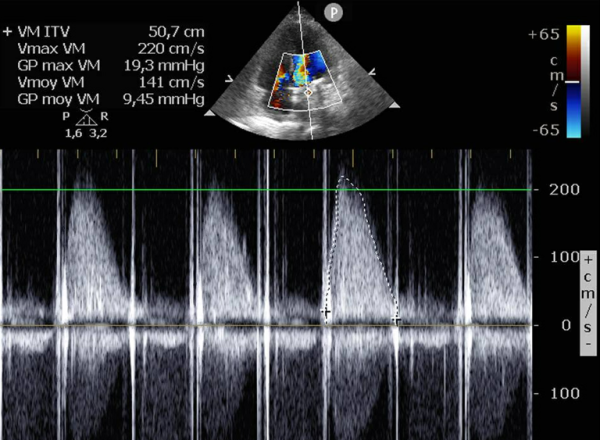

- ETT de sortie : élévation du gradient transmitral avec aspect de blocage d'une ailette mitrale (latérale - vers l'ancienne commissure antérieure)

ETT + ETO

Figure 1